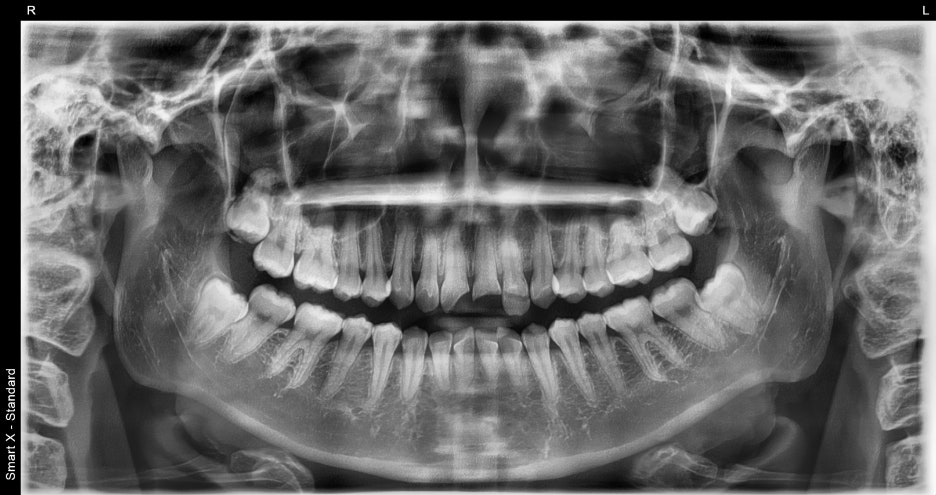

진단 결과

상악 앞니 4개 치아 파절 확인되었으며

일부 치아는 신경이 노출되어 신경치료 필요하고,

심한 변색과 파절로 인해 단순 레진 수복보다는

크라운 수복이 적합하다고 판단하였습니다.